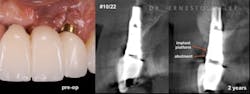

Figure 1: Patient reported discomfort and periodic fistula on labial mucosa of Nos. 10/22. Existing bridge is 12 years old, with implant Nos. 9/21 submerged. Previous history of failed implants/GBR in same area. Buccal plate regeneration was achieved with SMART bone graft. Stable bone volume and no symptoms after two years.

Anorganic bovine bone xenograft particles are mixed with recombinant human platelet-derived growth factor (rhPDGF-BB). The combination is delivered into the subperiosteal pouch with a specially configured carrier and compacted. No marrow penetration, space-making devices, or membranes are required. Particle aggregation within the pouch results in horizontal bone augmentation lateral to the exposed implant surface (figure 1).